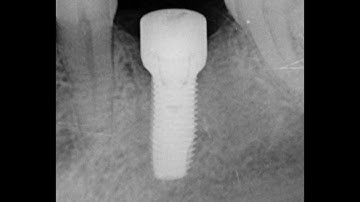

The return of tissue level implants